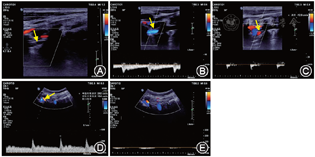

临床资料 患者男性,25岁。因突发头晕、头痛5 d于2019年9月29日就诊。患者无明显诱因突发头晕,右侧转颈时加重,伴有明显的视物旋转感,恢复中立位时头晕可缓解。2 d前曾在外院就诊,头部MRI、MRA示双侧小脑多发梗死,右侧病灶范围较大;MRA提示右侧椎动脉未显影,双侧大脑后动脉均发自同侧颈内动脉,左侧大脑前动脉A1段未显示(右侧共干)。既往无高血压、糖尿病、脑血管病、心脏病病史;否认风湿及自身免疫性疾病史,平时无颈部疾病及按摩史,病前无颈部疼痛、外伤、手术、放化疗病史;吸烟5年(2~3支/d),机会饮酒。否认家族遗传史及类似疾病病史。入院诊断:青年不明原因卒中待查。入院后体格检查:生命体征及血压正常,心肺检查未见异常;颈部和眶内无杂音。神经系统体检:脑神经正常,四肢肌力Ⅴ级、肌张力正常, 四肢腱反射适中, 双侧巴宾斯基征(-);深浅感觉及共济检查未见异常。患者身高175 cm、体重75 kg。住院期间患者多次于转颈时反复出现头晕、头痛明显加重,但发作时未见确切的神经系统定位体征,恢复中立位后症状迅速缓解。辅助检查:血常规、生化全项及甲状腺功能、糖化血红蛋白、凝血四项、自身免疫抗体、肿瘤标志物均未见异常,但血浆同型半胱氨酸明显升高[45.96(正常值:3.70~13.90)μmol/L]及类风湿因子水平升高[31.2(正常值:0~20.0)U/ml]。入院后进一步行心电图及经胸心脏超声、对比增强经颅多普勒超声(发泡,仰卧位)检查均未见异常(2019年9月29日)。进一步行颈部血管彩色多普勒超声(CDU)检查(2019年9月29日,图1A~E),结果仍提示右侧椎动脉节段性闭塞;向右侧转颈至近90° 过程中,左侧椎动脉V2段血流速度及频谱形态从正常迅速变为舒张末期血流信号消失的“低流速高阻力”频谱形态,同时寰枢椎段管腔受压变窄,狭窄以远呈缺血改变,恢复中立位后椎动脉血流速度及频谱形态也恢复正常。为明确寰枢椎段椎动脉管腔受压变窄的原因,行颈段MRI检查(2019年9月29日;图2A、 B),提示可疑寰枕关节融合、寰枢关节脱位及枕骨大孔狭窄。进一步经右侧股总动脉穿刺行全脑数字减影血管造影(DSA),获取3D DSA(图3)图像的同时获得C臂CT (Dyna-CT,图4)图像信息,结果DSA可见 V1~2段断续显影,于C1~2水平闭塞,颅内段椎动脉未见显影,提示右侧椎动脉夹层可能性大(图3A),颈部中立位时左侧椎动脉管腔通畅并汇入基底动脉(图3B);令患者向右侧转颈45~90°过程中,患者头晕再次加重,同时显示左侧椎动脉在C1~2水平明显受压、管腔变窄(图3C),左侧椎动脉颅内段显影浅淡,基底动脉部分显影至消失(图3C)。根据患者上述旋转性头晕发作病史,结合颈部血管CDU及DSA于头颈部旋转后出现椎动脉特殊的血流动力学变化特点,临床诊断考虑为BHS并颅内段椎动脉夹层所致的双侧小脑梗死可能性大。住院期间给予患者阿司匹林及氯吡格雷双联抗血小板、限制颈部转动以及佩戴颈托等保守治疗,同时根据外科会诊建议(行手术治疗解除血管受压),向患者交代病情。但患者要求药物保守治疗,拒绝手术。2周后患者头晕症状基本好转出院。出院时嘱患者避免颈部剧烈旋转动作。出院后1个月随访,患者病情基本稳定,偶发头晕。

本例患者为青年男性,有吸烟、机会饮酒史,平素身体健康,无明确的心脑血管疾病史;本次以发作性转颈后头晕为主要表现,心电图、经胸心脏超声以及TCD发泡检查结果均未见异常,头部MRI提示双侧小脑半球多发梗死灶,可以诊断为不明原因的青年卒中,根据既往病史、体检及心脏超声、心电图检查,可以除外双侧小脑半球梗死的心源性病因。患者双侧后循环血管受累,血液类风湿因子及同型半胱氨酸水平明显升高,应注意除外风湿系统或代谢系统性疾病的存在及其引起的血管炎。颈部血管彩色多普勒超声及头颅MRA均提示右侧椎动脉闭塞,考虑为右侧小脑半球梗死的责任病变血管,DSA证实颅内段右侧椎动脉闭塞可能为夹层所致。患者眩晕与转颈动作有明确的关系,CDU显示中立位与转颈交替体位变化后,左侧椎动脉呈间歇性闭塞改变,支持BHS诊断。有报道BHS在CDU中的特征性表现为颈部处中立位时,V2段椎动脉血流速度及频谱形态均正常,颈部旋转时V2段舒张期血流逐渐下降至消失,转变为低流速高阻力小脑后下动脉前闭塞的血流模式,这种动态的血流动力学变化应高度怀疑BHS[21]。本例患者在转颈过程中可见左侧椎动脉V2段血流速度及频谱形态从正常逐渐转变为舒张末期血流信号消失的低流速高阻力“单峰”血流频谱,同时可见左侧寰枢椎段管腔受压变窄,狭窄以远呈缺血变化;恢复中立位后上述血流速度及频谱形态再次恢复正常,符合BHS的血流动力学变化。